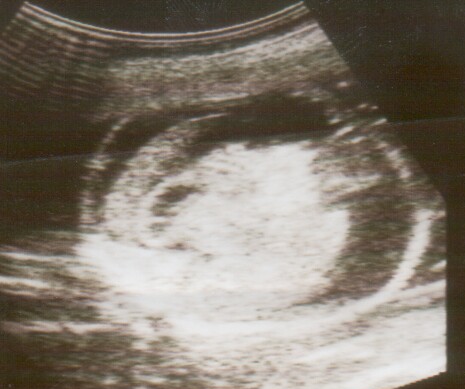

上個月初,喬安娜.蓋恩斯興奮地在她的Instagram帳號上傳了一張胎兒超音波照片,與粉絲們正式宣告她與奇普的第五個孩子即將降臨,為之興奮的節目粉絲紛紛推文按讚。在一片祝賀問候聲中,一位自稱是醫師的粉絲,善意地提醒喬安娜.蓋恩斯:從超音波照片中的細節推測,胎兒可能罹患了致命性的胎兒水腫(Hydrops Fetalis)。一瞬間,社群媒體中的歡欣氣氛急轉直下。